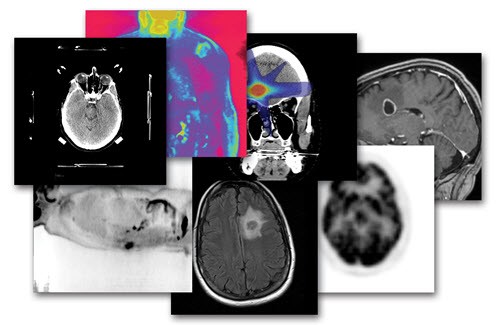

Con la finalidad de mejorar la precisión al máximo de los tratamientos de radioterapia, somos capaces de integrar los estudios de imagen del paciente, incluyendo tomografías contrastadas, resonancia magnética e incluso el moderno PET-CT, mediante poderosos programas de cómputo especializado, que fusionan estas imágenes en un solo plan maestro integral.